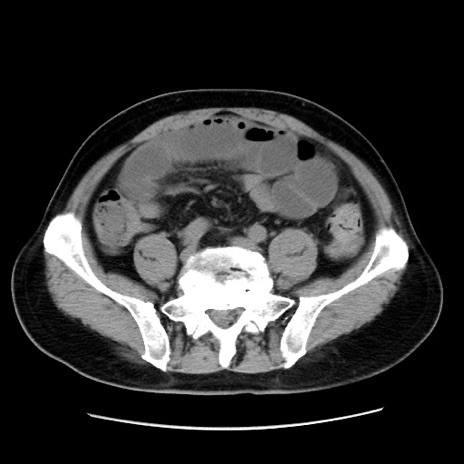

冠状断像